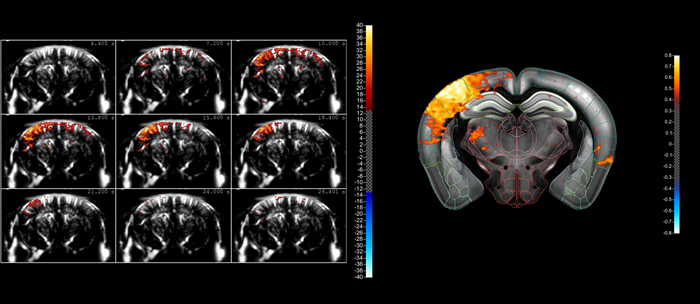

A typical compiled sequence of images acquired using fUS, showing the ‘lighting up’ of a part of the mouse brain as a result of whisker stimulation. The fact that blood flows in the brain can be in different directions within a small volume means that it’s better to image this activity using blood volume (using Power Doppler) rather than blood velocity (using color Doppler). However, our fUS– and microbubble-enabled ultrasound localization microscopy (ULM) technique – allows the actual blood velocities to be determined at high resolution should that information be needed

A typical compiled sequence of images acquired using fUS, showing the ‘lighting up’ of a part of the mouse brain as a result of whisker stimulation. The fact that blood flows in the brain can be in different directions within a small volume means that it’s better to image this activity using blood volume (using Power Doppler) rather than blood velocity (using color Doppler). However, our fUS– and microbubble-enabled ultrasound localization microscopy (ULM) technique – allows the actual blood velocities to be determined at high resolution, should that information be needed. Image Credit: Iconeus